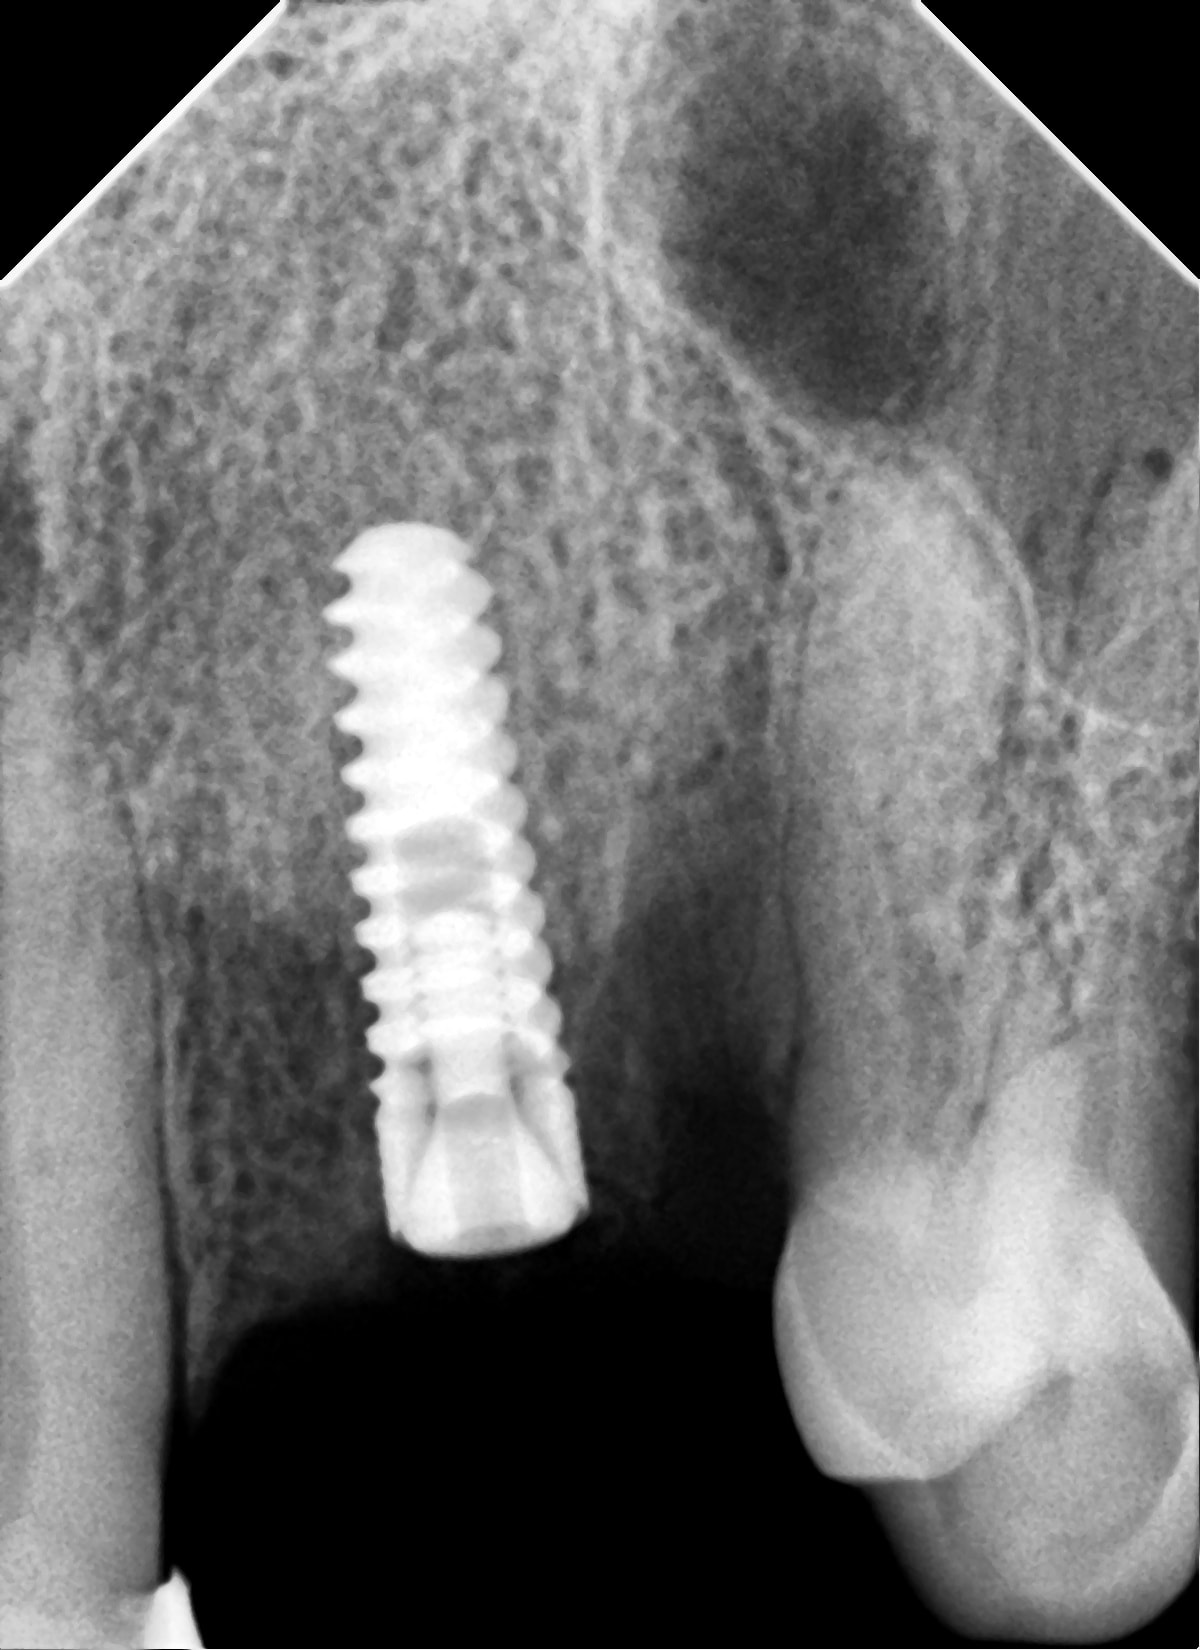

د. مالك علي - زراعة TB Implant System في الفك العلوي

د. مالك علي - تم تركيب زرعة TB Implant System في الفك العلوي الأمامي لتعويض فقد سن أمامي مع زراعة مؤجلة.